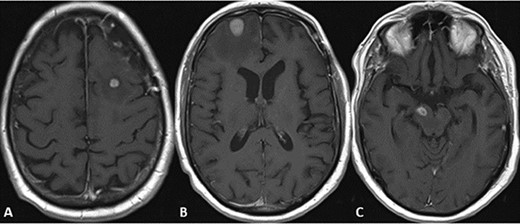

CASE

Postoperative CT and MRI scans of the head indicating complete tumor resection with reduced midline shift.